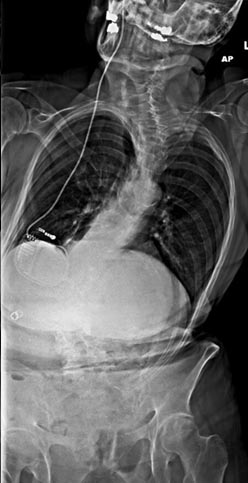

41 year old male with metastatic renal cell carcinoma to the spine presenting with cord compression

Painfree after corpectomy and decompression of the spinal cord.